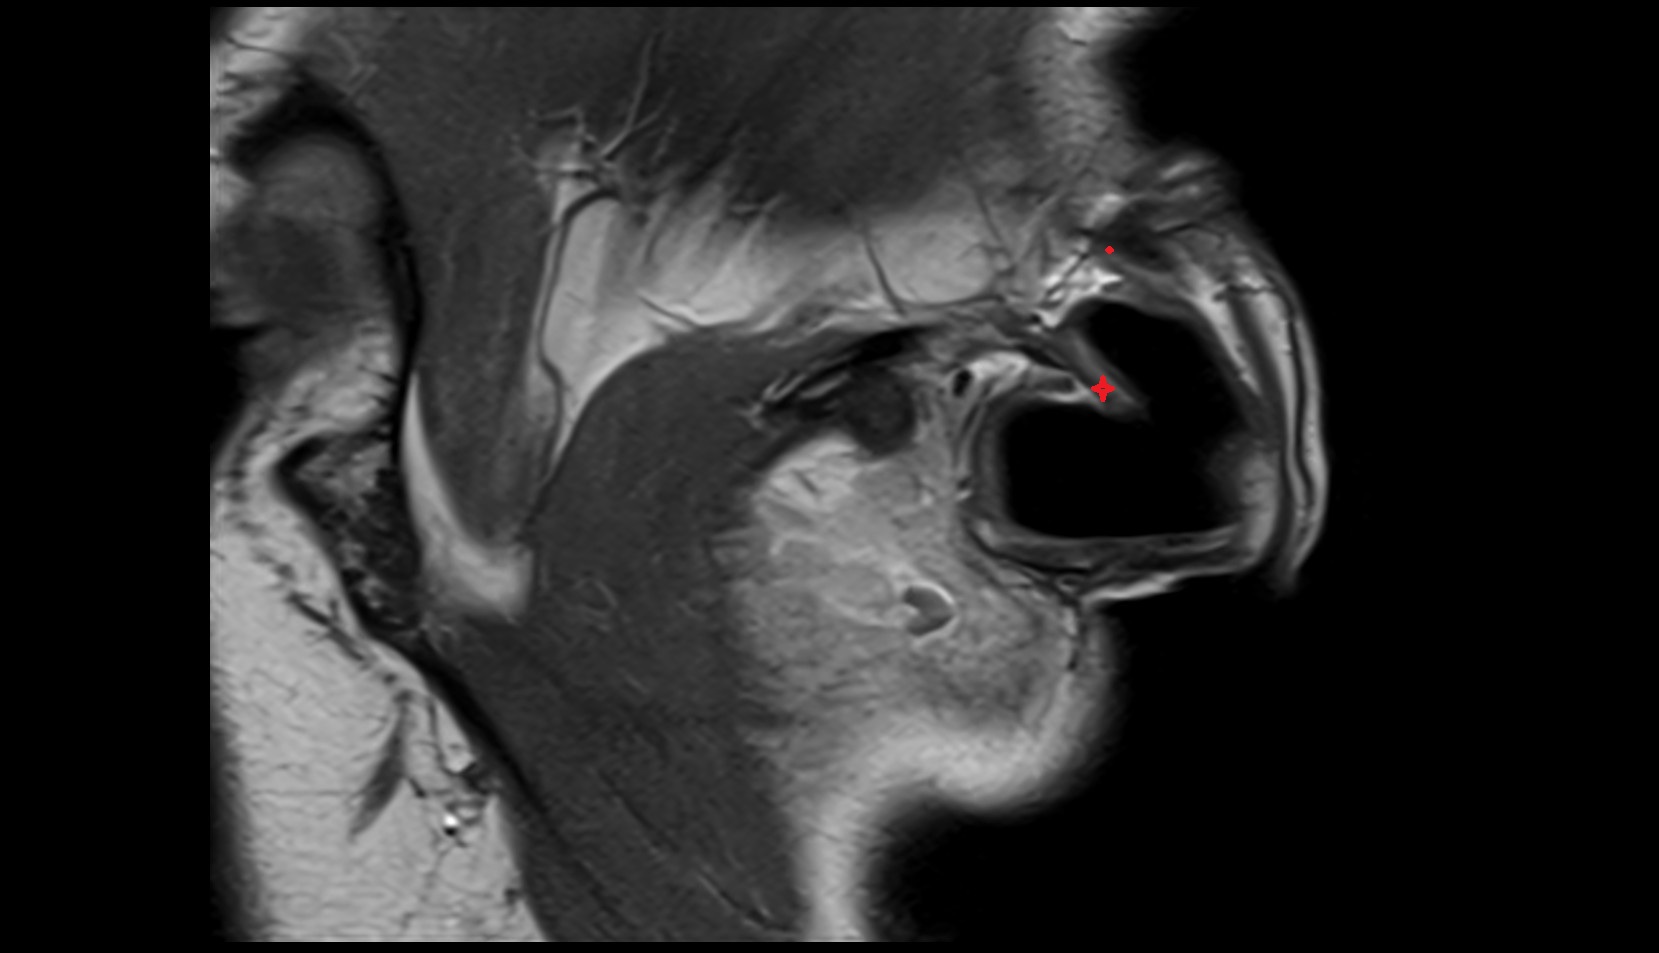

- Temporomandibular joint

- Articular disc of temporomandibular joint

- Articular eminence

- Mandibular condyle

- Mandibular fossa

- Superior head of lateral pterygoid muscle

- Inferior head of lateral pterygoid muscle